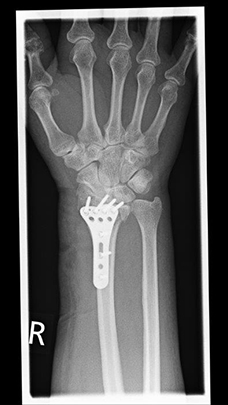

Radiusfraktur nach Korrekturoperation

Radiusfraktur nach Korrekturoperation Frontalansicht